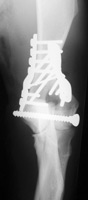

• multi-modal fracture repair

(please click on photos to enlarge)